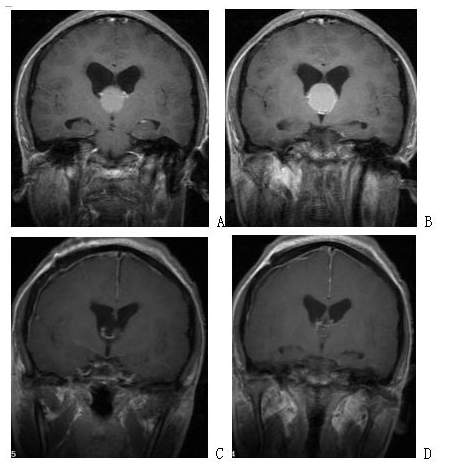

Figure 2. Enhanced MRI before surgery in A and B suggests recurrent giant full-slope chordoma; enhanced MRI after endoscopic transnasal surgery in C and D suggests complete tumor resection.